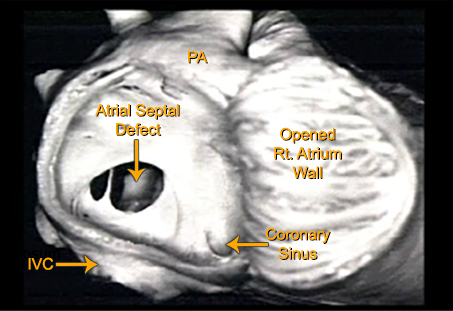

This is a pathology specimen from a patient with a secundum atrial septal defect. The large right atrium has been opened exposing a large defect. A remnant of the septum primum with two large holes is seen bridging the defect. Also seen are the inferior vena cava, the coronary sinus and the pulmonary artery